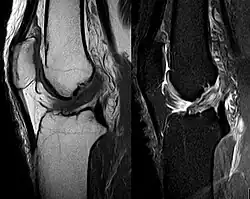

Die Diagnose kann mit bildgebenden Verfahren – namentlich der Magnetresonanztomographie (MRT, „Kernspin“) – bestätigt werden. Dabei ist allerdings zu beachten, dass die Interpretation der MRT in der Diagnostik eines Kreuzbandrisses zu 20 Prozent falsche Diagnosen liefert. Hier kommt es auf die sogenannten Schnittbilder und die geeignete Positionierung des Kniegelenkes bei der MRT-Untersuchung an. Der Radiologe sollte die genaue Vorgeschichte kennen, die zur Verletzung führte, und auch Erfahrung in der Untersuchung eines verletzten Gelenkes haben, um Fehlbeurteilungen zu vermeiden. Im Vergleich zur MRT liegt die Fehlerquote bei dem erheblich einfacher durchzuführenden Lachman-Test bei nur 10 Prozent.[85][86][87][88] Die MRT ist daher in der Regel zur Diagnose eines vorderen Kreuzbandrisses weniger sensitiv und weniger spezifisch als die klinische Befundung durch einen qualifizierten Orthopäden.[89] Das Ergebnis einer MRT hat nur relativ selten einen Einfluss auf die klinische Entscheidungsfindung[90] und sollte keinen Ersatz für eine sorgfältige Anamnese und Palpation darstellen.[15] Mehrere Studien kommen zu dem Schluss, dass eine MRT nur bei komplizierteren unklaren Knieverletzungen – und dabei eher zum Erstellen einer Ausschlussdiagnose[91] – sinnvoll ist.[92][93]

Röntgenaufnahmen leisten keinen unmittelbaren Beitrag zur Diagnosestellung einer Kreuzbandruptur. Beide Kreuzbänder sind – ob gerissen oder nicht – im Röntgenbild nicht sichtbar. Wird dennoch geröntgt, so kann dies der Diagnosestellung von möglichen knöchernen Begleitverletzungen dienen.